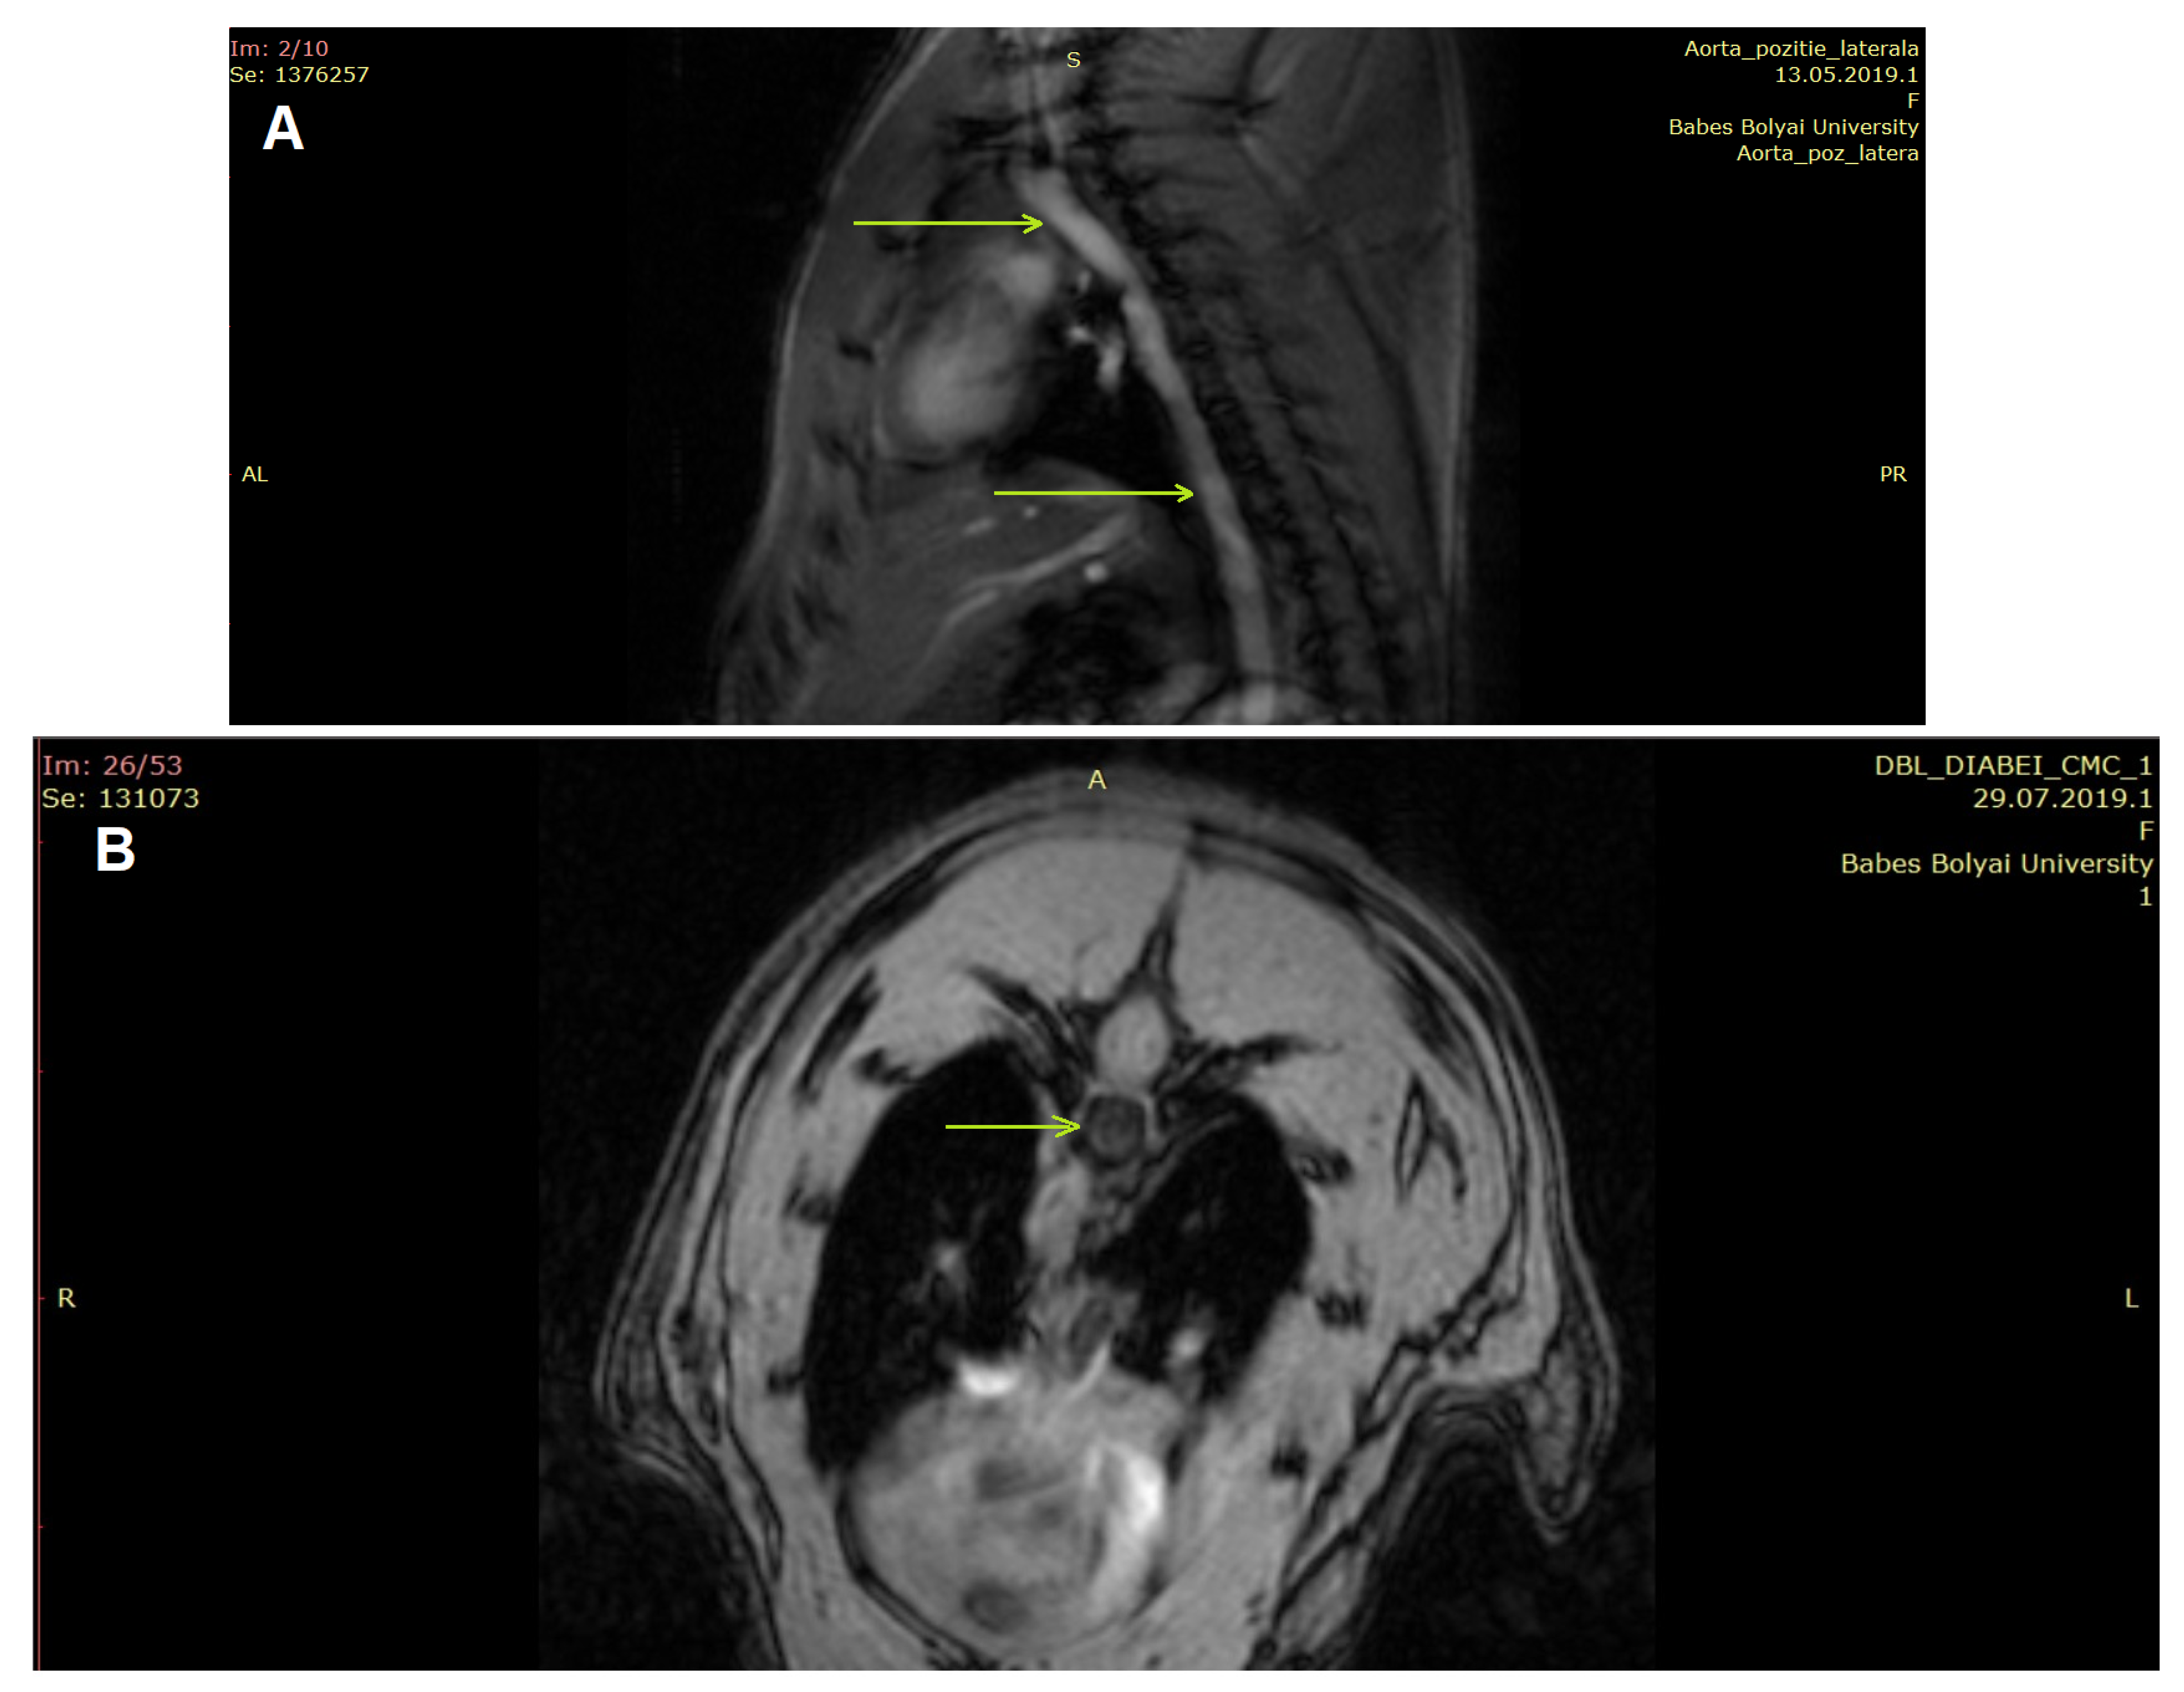

3.3.2. IntraGateFlash CINE Scanning Investigation